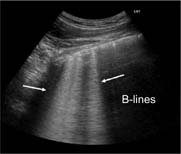

Well-separated B-lines (Figure 6): one of the hallmarks of acute lung injury is increased extravascular lung water (EVLW), which extends to the lung peripheries. This produces vertical ultrasound artefacts resulting from abnormal gas–tissue interface. B-lines start from the pleural line and “shine” vertically to erase A-lines and reach the end of the screen. The presence of B-lines reflects moderate lung aeration loss resulting from interstitial syndrome. B-lines are often sparse and separated.

FIG 6. B-lines.